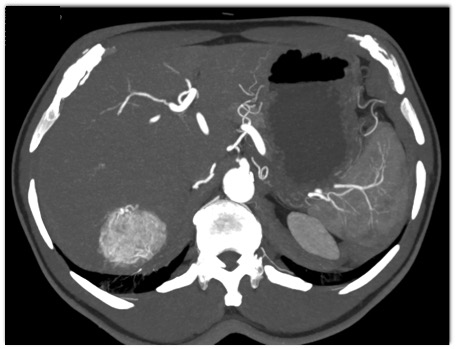

The least likely diagnosis in this case is?

focal nodular hyperplasia

hepatic adenoma

hemangioma

hydatid cyst